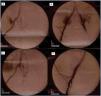

Las analíticas iniciales mostraron una anemización de 4 puntos con respecto a su hemoglobina basal. Se le realizó una ecografía abdominal urgente en la que se objetivó hemoperitoneo sin un origen claro. Se sometió a la paciente a tomografía computarizada (TC) abdominal con contraste. Se visualizó injerto renal en fosa ilíaca izquierda y una formación pseudoaneurismática de 4,4 x 5 x 5,2 cm (diámetro transversal, anteroposterior y craneocaudal) con un cuello dependiente de la arteria ilíaca externa derecha y abundante hemoperitoneo a nivel perihepático, periesplénico, en ambas gotieras y en pelvis, siendo estos hallazgos compatibles con pseudoaneurisma roto (figura 1).

Figura 1. Tomografía axial computarizada abdominal